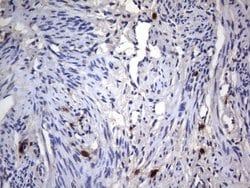

CD68 Mouse anti-Human, Clone: KP1, liquid, TrueMAB™

CD68 (Macrosialin) is a 110 kDa integral membrane glycoprotein predomitly expressed on the intracellular lysomsomes of monocytes and macrophages and to a lesser extent by dendritic cells and peripheral blood granulocytes. Also, CD68 could play a role in phagocytic activities of tissue macrophages, both in intracellular lysosomal metabolism and extracellular cell-cell and cell-pathogen interactions. CD68 is expressed by interdigitating reticulum cells in tonsil and some histiocytic lymphoma or histiocytosis, acute myeloid leukemia (AML), and granulocytic sarcoma. Elevated expression of CD68 has been demonstrated on CD34+ cells in various human maligcies, including several Acute Myeloid Leukemia studies.Specifications

Flow Cytometry, Immunohistochemistry (Paraffin) | |

KP1 | |

Lysosomal fraction of human lung macrophages CD68(KP1) | |